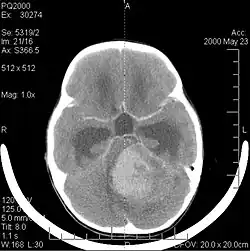

W niemal 75% przypadków lokalizuje się w robaku móżdżku. Guz blokując przepływ płynu mózgowo-rdzeniowego daje objawy wzmożonego ciśnienia śródczaszkowego, a zajęcie móżdżku powoduje zaburzenia chodu. Rozprzestrzenia się podpajęczynówkowo, nie tylko w tylnym dole czaszki, ale nad całym mózgiem i rdzeniem kręgowym. Makroskopowo ma postać ciemnoczerwonej, luźnej konsystencji (przypominającej galaretę) masy. U starszych dzieci częstszą lokalizacją są półkule móżdżku.